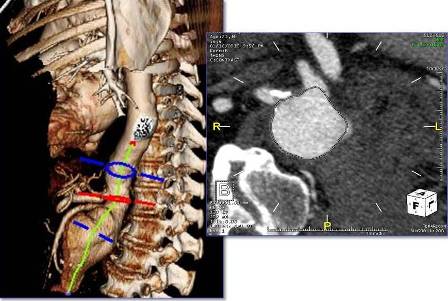

Using the most advanced, three-dimensional reconstruction

software, a custom-made endograft is planned and designed

for your patient’s specific anatomy.

Examples of Some of Our Recent Cases

For complex aneurysms (those aneurysms which include portions of the aorta with branch arteries that supply organs such as the kidneys and intestines), a special type of repair is required to preserve flow to these branch arteries: a fenestrated endograft, with special holes placed in the endograft at the precise location in which these branches arise. The fenestrated endograft is designed specifically to fit each patient’s particular anatomy; this is possible through the use of sophisticated imaging software that allows Dr Schanzer and his team to manipulate the CT images obtained of the patient’s aorta and branch arteries.

The fenestrated endograft, designed specifically for the particular patient, is then positioned inside the aorta from within the blood vessels in the groin; this allows for the aorta to be “re-lined”, with the holes positioned precisely to allow blood to continue to flow into the branch arteries, while blood flow no longer fills the aneurysm sac.

Some of the intraoperative techniques that facilitate this approach include the use of a state-of-the-art hybrid operating room. A CT scan is performed right in the OR; these images are merged with the preoperative CT scan images using “fusion” technology. This technology enhances the safety of the procedure by allowing Dr Schanzer and his team to minimize the amount of radiation and contrast dye that is used in the procedure.